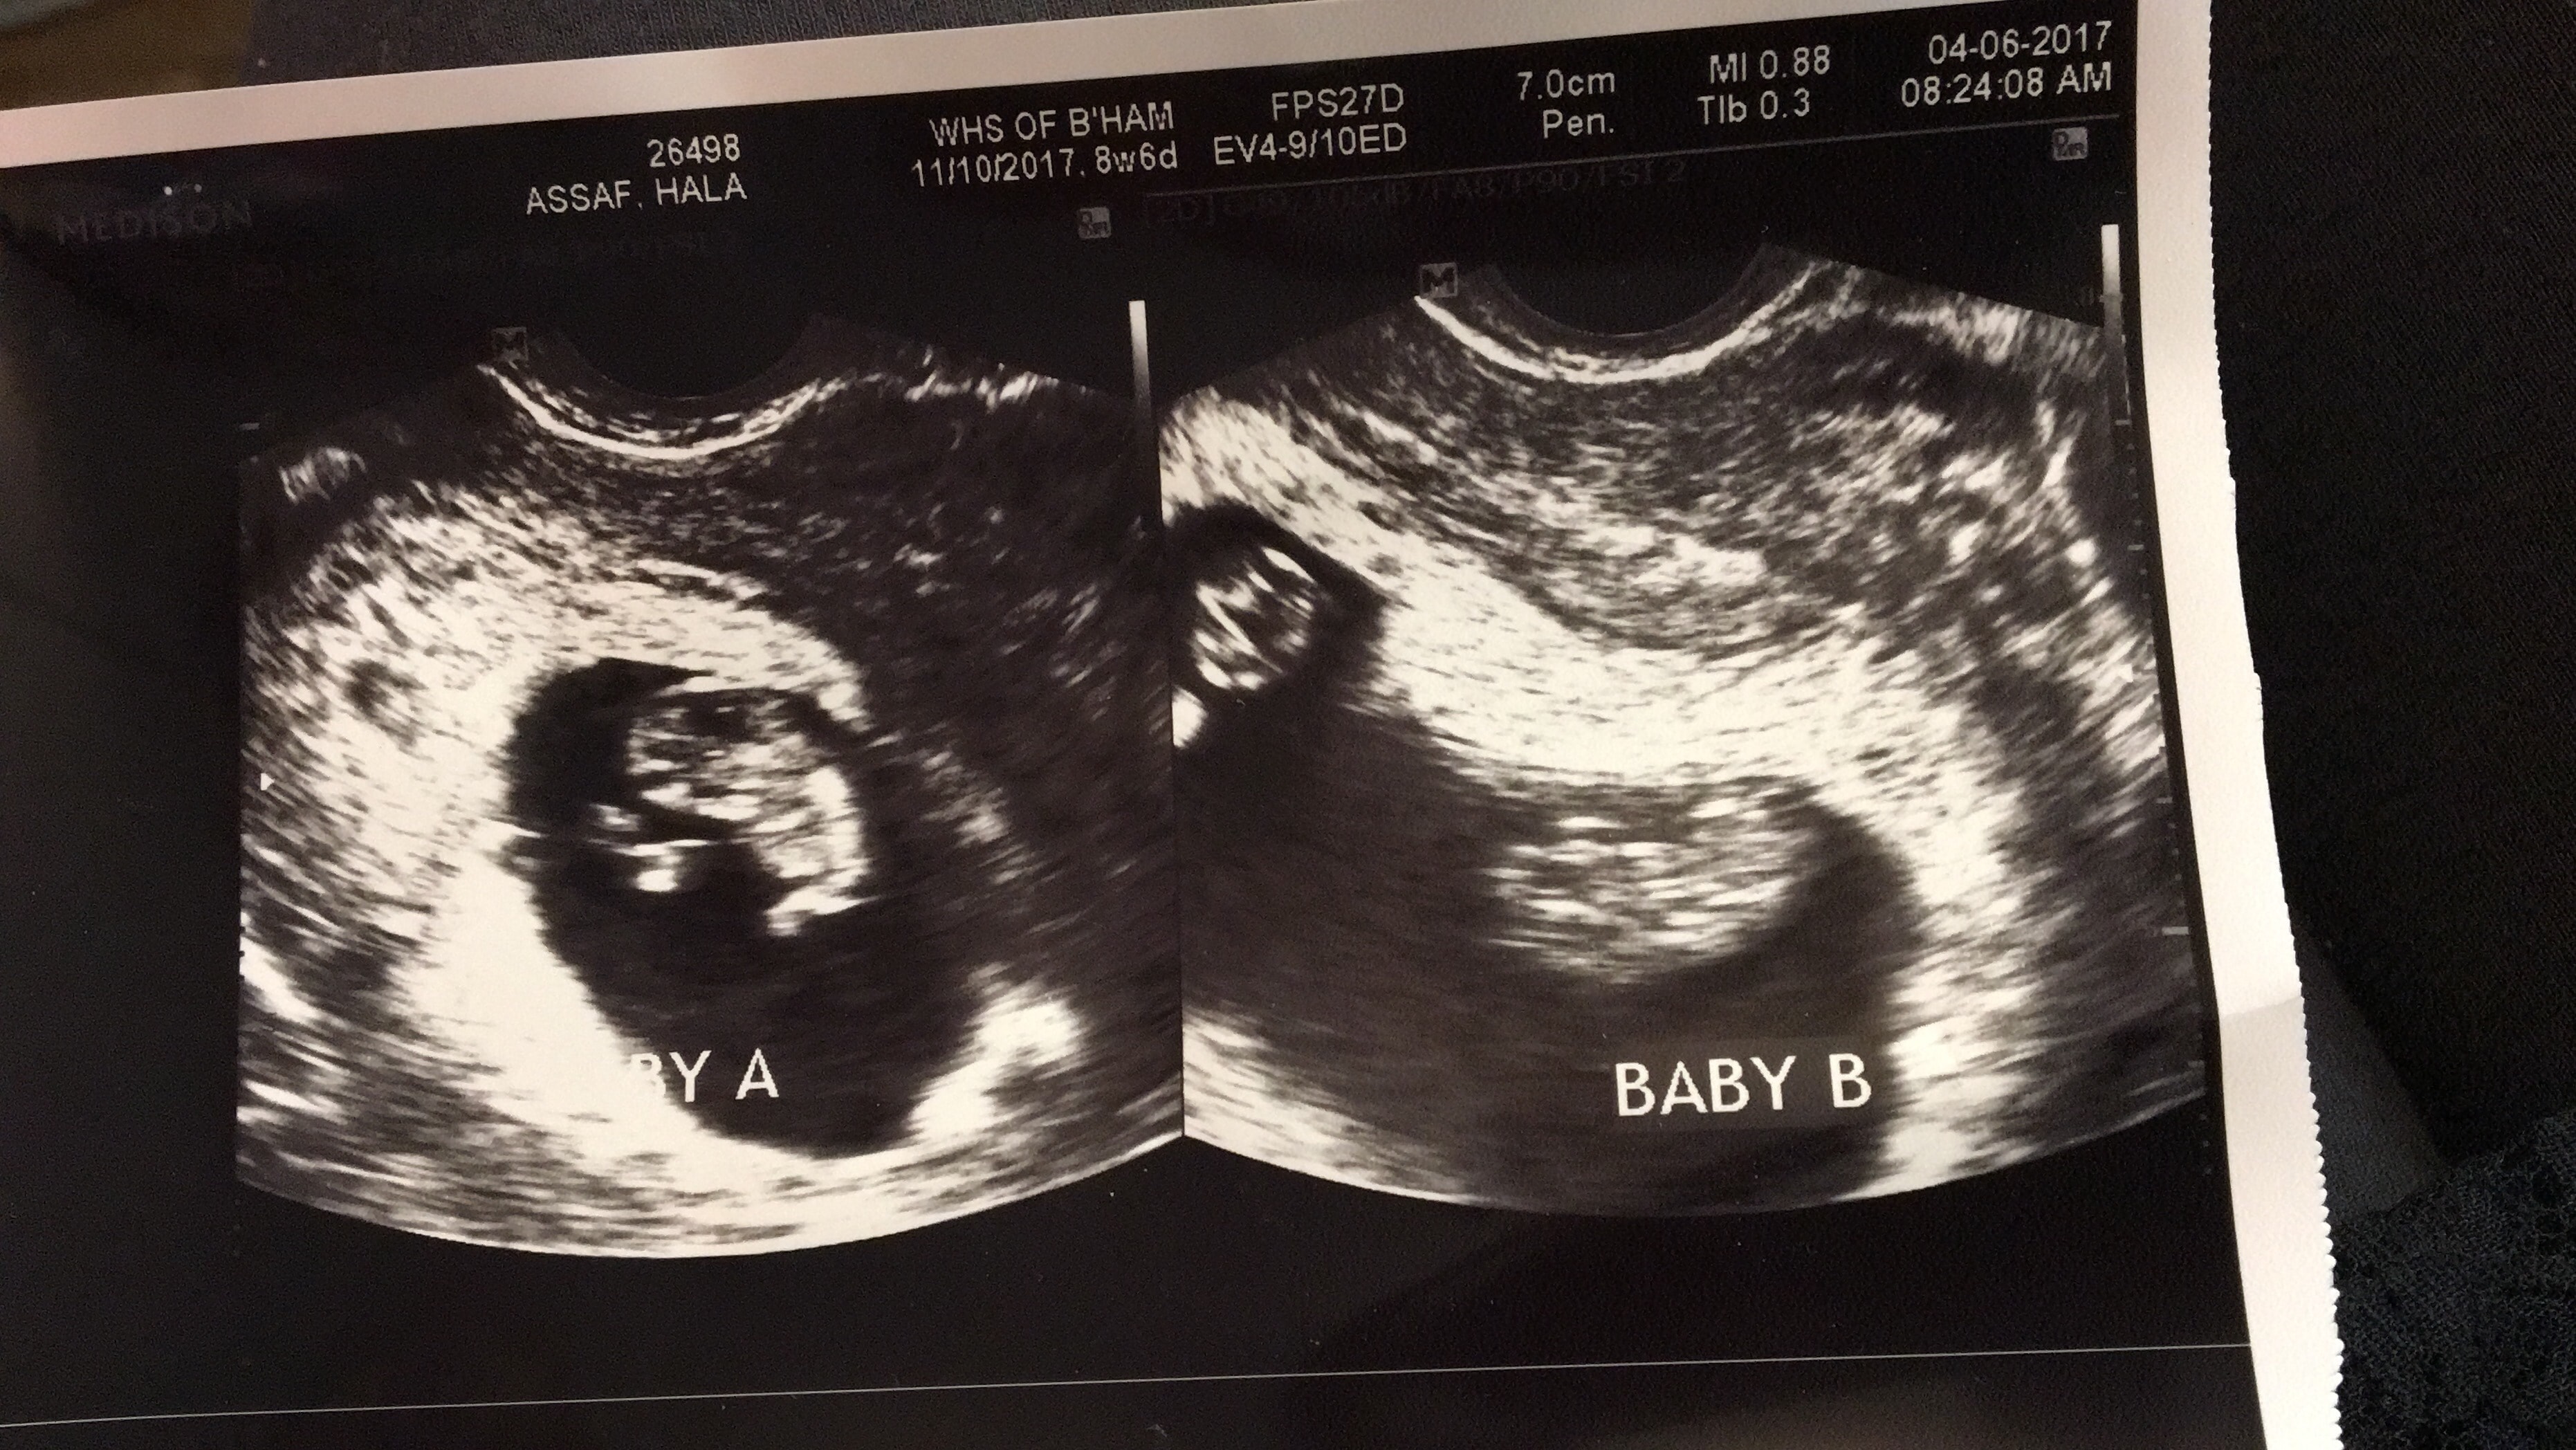

Ultrasound Photos of 9 Weeks Pregnant With Twins